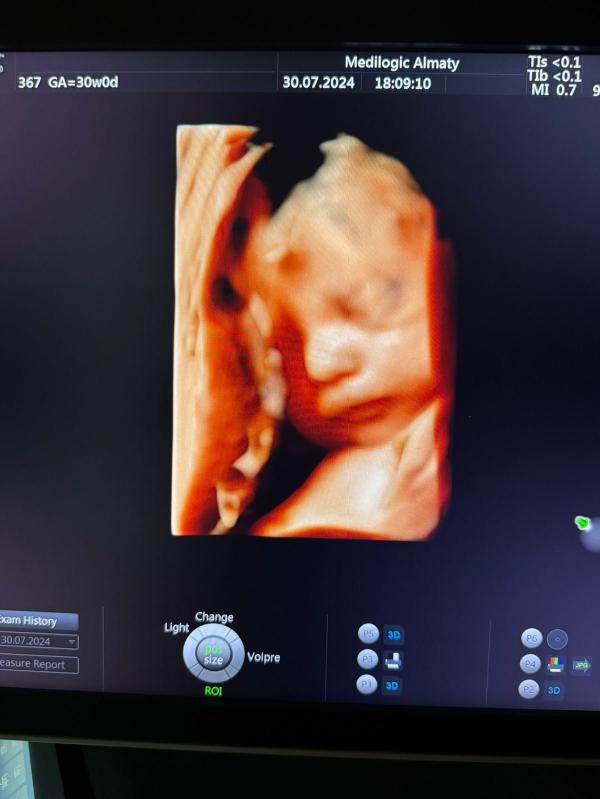

Вчера делала узи для 3 скрининга. Узист еще сделал на память 4 д снимок. Такой малютка. Вообще кажется похож на младшую. Все таки рождение это чудо. Дай Аллах до конца без проблем выходить, чтобы он рос как прложено и родить с легкостью здорового малыша всем.